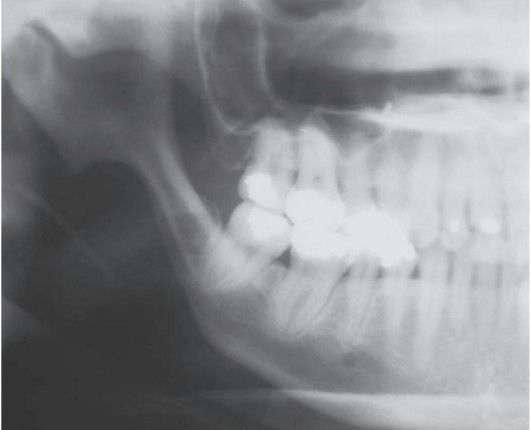

Scleroderma XRAY

Scleroderma leads to resorption of mandibular ramus.